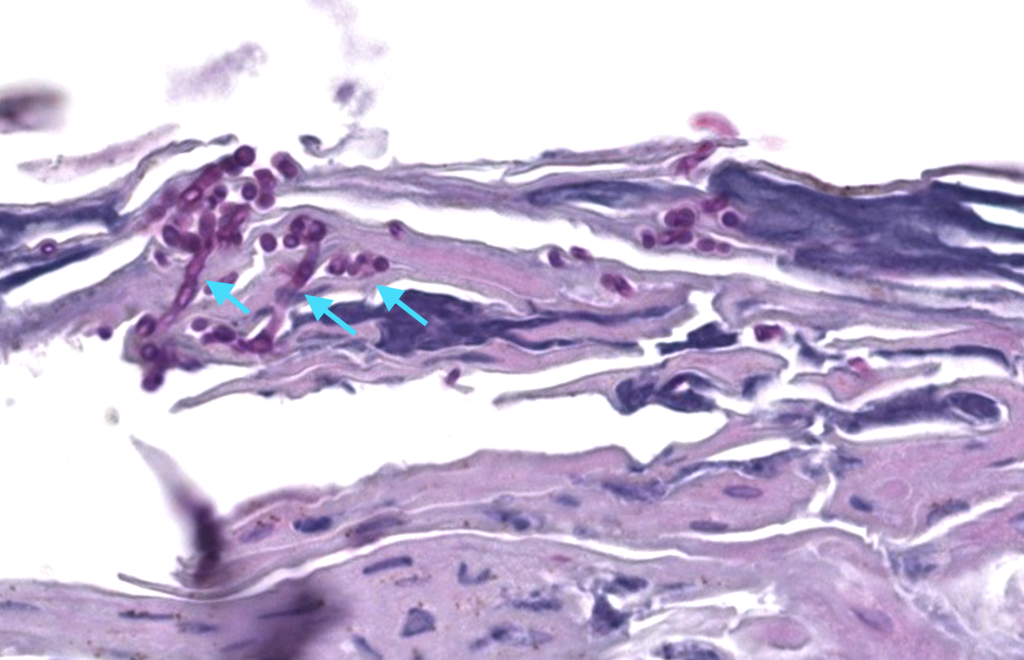

Patrón: infección a nivel de estrato córneo superficial.

Descripción: esporas + hifas cortas y curvadas en estrato córneo (“spaghetti & meatballs”); leve dermatitis perivascular superficial.

Tinciones: PAS y GMS intensifican visualización. DIF no indicada

- Dermatofitosis (hifas filamentosas continuas en estrato córneo, sin mezcla típica de esporas),

- Malassezia foliculitis (levaduras dentro del infundíbulo con reacción perifolicular),

- Eritrasma (bacilos corinebacterianos; PAS-negativos).